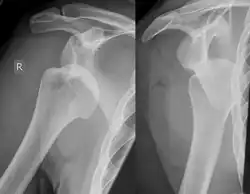

Lesão de Hill-Sachs, ou Fratura Hill-Sachs, é uma depressão cortical na cabeça do úmero posterolateral. É o resultado de impactação forte da cabeça umeral luxada contra a glenóide anterior quando o úmero é luxado anteriormente.

A lesão está associada exclusivamente com a luxação glenoumeral anterior.[2] Quando o úmero é impulsionado à partir da cavidade glenoumeral, este impacta a cabeça, relativamente macia contra a borda anterior da glenóide. O resultado é um torrão, sulco ou achatamento no aspecto posterolateral da cabeça do úmero, geralmente oposto ao processo coracóide. O mecanismo que leva à luxação do ombro é geralmente traumático, mas pode variar, especialmente se houver história de deslocamentos anteriores. Esportes, quedas, convulsões, brigas ou virar na cama podem ser causas de deslocamento anterior.